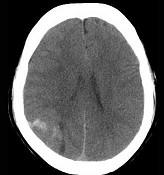

问题 男,37岁,头痛、头晕1年余,加重3天,CT检查如图所示,最可能的诊断为()

选项 A.脑出血 B.脑血管畸形并出血 C.脑膜瘤并出血 D.颅内动脉瘤 E.转移瘤并出血

答案 C